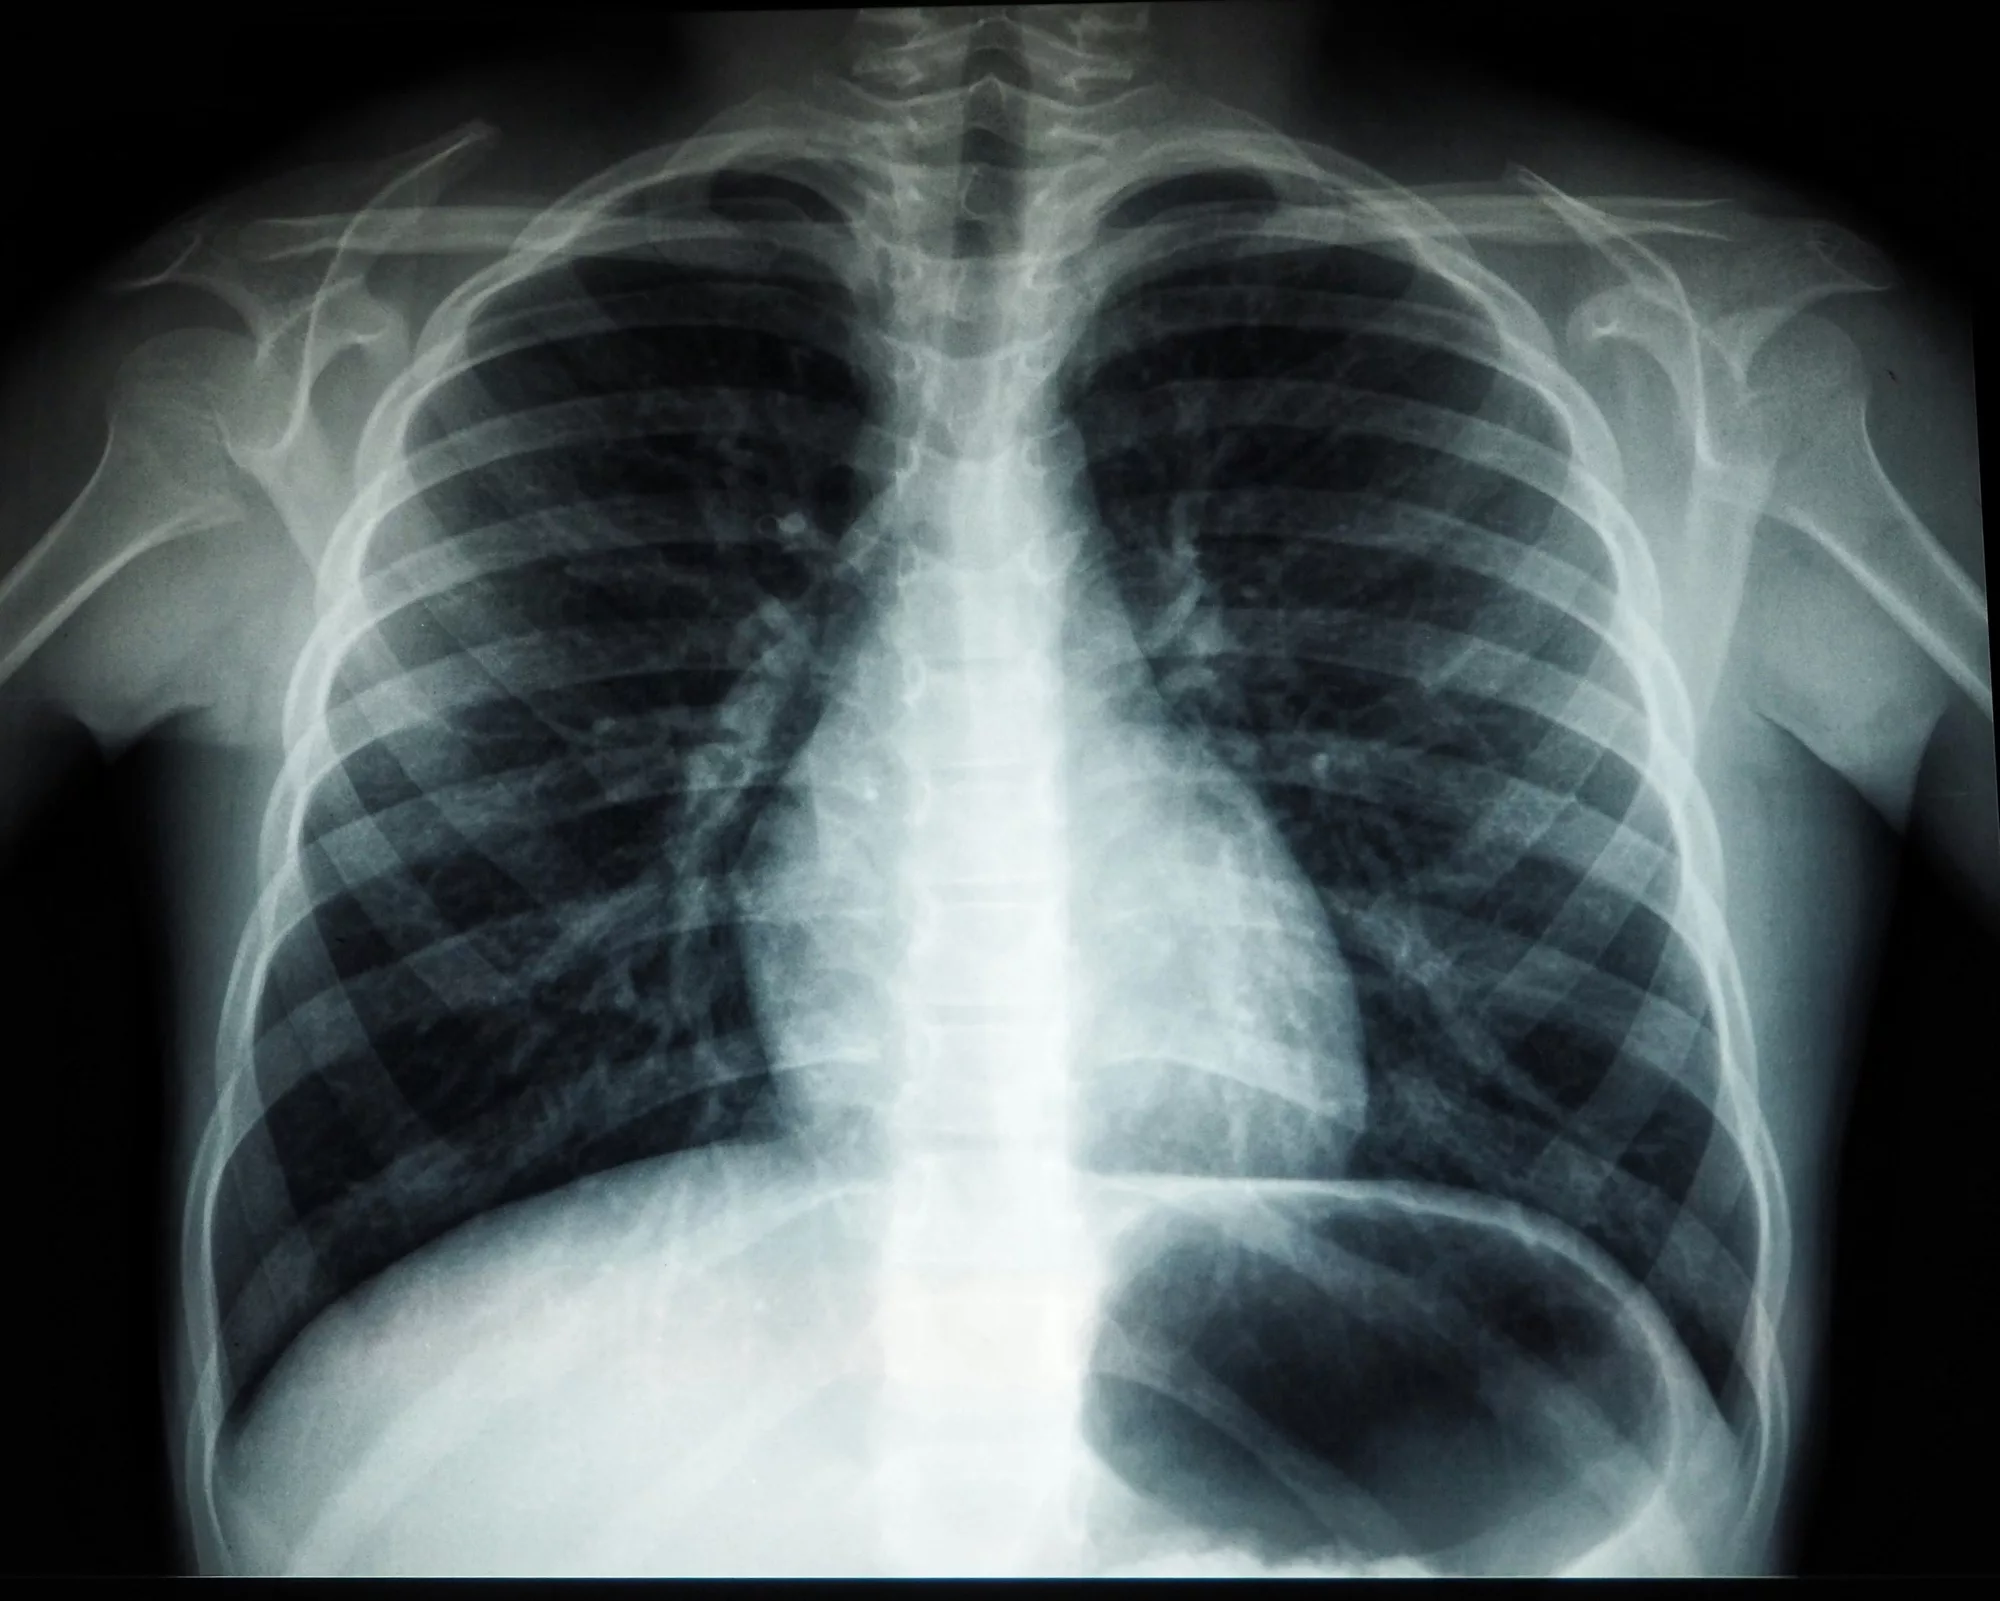

Radiography, often associated with X-rays, relies on ionizing radiation to create images of the body’s internal structures. It is particularly effective for visualizing bones, detecting fractures, and identifying abnormalities in the chest or abdomen. On the other hand, sonography, also known as ultrasound, uses high-frequency sound waves to produce real-time images, making it invaluable for examining soft tissues, monitoring pregnancies, and guiding certain medical procedures.

Radiography is a medical imaging technique that uses ionizing radiation, primarily in the form of X-rays, to create images of the body’s internal structures. When X-rays are directed at the body, they pass through tissues at varying degrees depending on the tissue’s density. Dense materials like bones absorb more X-rays and appear white on the resulting image, while less dense tissues like muscles or fat allow more X-rays to pass through, appearing in shades of gray.

- Chest X-Rays: Diagnosing conditions like pneumonia, tuberculosis, or lung cancer.